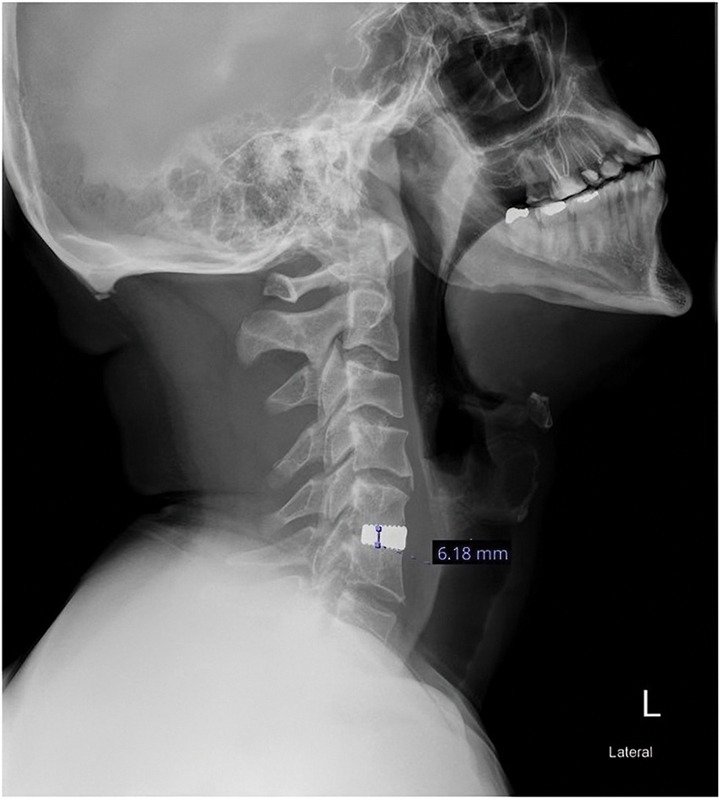

背景颈椎前路椎间盘切除术和融合术(ACDF)是退行性颈椎病和脊髓型颈椎病最常用的神经减压技术之一。关于颈椎前板笼增强术的优越性仍然存在争议,但一些外科医生仍在使用独立笼(ACDF- sa)进行ACDF。我们的研究目的是比较单节段颈椎退变椎间盘病变的ACDF加前颈椎钢板(ACDF- cpa)和ACDF- sa的影像学结果。方法回顾性分析2011年1月至2019年12月间行ACDF的患者资料。所有接受单级ACDF治疗颈神经根病和脊髓病且随访至少12个月的成年患者均被纳入研究。有全身性感染、外伤、恶性肿瘤病史、x线片检查不充分、随访时间少于12个月的患者被排除在研究之外。放射学结果,包括笼沉降、融合率和邻近节段退变,由两名高级骨科脊柱研究员评估。校正风险比用于比较ACDF-SA和ACDF-CPA的放射学结果,并对年龄和性别进行校正。结果共纳入43例患者。其中,58%的患者接受了独立式cage ACDF, 42%的患者接受了颈椎前板增强术。6个月时的总融合率为76%。ACDF-SA组融合率为88%,ACDF-CPA组融合率为61%。12个月时,两组的整体融合率为81%,具有可比性。6个月和12个月时,两组鼠笼下沉率和相邻节段退变率相似。调整后的相对风险分析显示,与ACDF-CPA组相比,ACDF-SA组6个月的融合概率高50%(95%可信区间[CI]: 1.01-2.22), 12个月的融合概率高22%,但无统计学意义(95% CI: 0.90-1.64)。女性在12个月时具有较高的融合率和较低的下沉风险。结论在单节段ACDF中,颈椎前板增强术并不比传统的独立式椎笼具有优势。我们的研究显示了类似的笼沉降、邻近节段疾病和12个月融合率的结果。然而,独立笼在6个月时的融合速度比钢板组快。

Background  Anterior cervical discectomy and fusion (ACDF) is one of the most commonly used techniques for neural decompression in degenerative cervical radiculopathy and cervical myelopathy. Controversies regarding the superiority of cage augmentation with anterior cervical plate remain, yet several surgeons are still performing ACDF with a stand-alone cage (ACDF-SA). Our study aimed to compare the radiological outcomes between the ACDF augmented with anterior cervical plate (ACDF-CPA) and ACDF-SA in single-level cervical degenerative disc disease. Methods  A retrospective data review was conducted for patients who underwent ACDF between January 2011 and December 2019. All adult patients who underwent single-level ACDF for cervical radiculopathy and myelopathy with at least 12 months of follow-up were included in the study. Patients who had a systemic infection, trauma injury, history of malignancy, inadequate radiographs, and less than 12 months of follow-up were excluded from the study. Radiological outcomes, including cage subsidence, fusion rate, and adjacent segment degeneration, were assessed by two senior orthopaedic spine fellows. Adjusted risk ratios were used to compare the radiological outcomes of ACDF-SA and ACDF-CPA, adjusting for age and gender. Results  A total of 43 patients were included. Among them, 58% of the patients underwent a stand-alone cage ACDF, while 42% had anterior cervical plate augmentation. The overall fusion rate at 6 months was 76%. The ACDF-SA group's fusion rate was 88%, while that of the ACDF-CPA group was 61%. At 12 months, the overall fusion rate was 81% and was comparable between the two groups. Cage subsidence and adjacent segment degeneration rates were similar between the groups at 6 and 12 months. Adjusted relative risk analysis showed a 50% higher probability of fusion at 6 months in the ACDF-SA group compared with the ACDF-CPA group (95% confidence interval [CI]: 1.01-2.22) and a 22% higher probability at 12 months, though not statistically significant (95% CI: 0.90-1.64). Female gender was associated with higher fusion rates and lower subsidence risk at 12 months. Conclusion  Augmentation with the anterior cervical plate in ACDF did not show superiority to the conventional stand-alone cage in mono-segmental ACDF. Our study showed similar outcomes regarding cage subsidence, adjacent segment disease, and fusion rates at 12 months. However, the stand-alone cage achieved faster fusion at 6 months than the plate group.